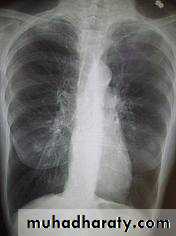

1-chest X-ray--- HRCT2- full blood count